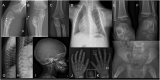

Parathyroid hormone-like hormone (PTHLH) plays an important role in bone formation. Several skeletal dysplasias have been described that are associated with disruption of PTHLH functioning. Here we report on a new patient with a 898 Kb duplication on chromosome 12p11.22 including the PTHLH gene. The boy has multiple skeletal abnormalities including chondrodysplasia, lesions radiographically resembling enchondromas and posterior rib deformities leading to a severe chest deformity. Severe pulmonary symptoms were thought to be caused by limited mobility and secondary sputum evacuation problems due to the chest deformity. Imaging studies during follow-up revealed progression of the number of skeletal lesions over time. This case extends the phenotypic spectrum associated with copy number variation of PTHLH.